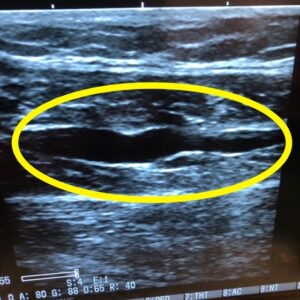

しかし、超音波エコーを用いると、損傷の部位や範囲、出血の有無などをその場で正確に確認することができます。

黄色い丸で囲まれた部分が肉離れ箇所で、

他に比べて黒く大きな画像が確認できます。

エコーは非侵襲的でレントゲンのような被ばくもなく、リアルタイムで筋肉の動きを観察できるのが大きな利点です。

当院でも初診時に必ずエコーを用いて状態を確認し、回復の過程も経時的に追っていきます。

これにより、無理のない運動再開やリハビリの進行を安全かつ的確に判断できます。